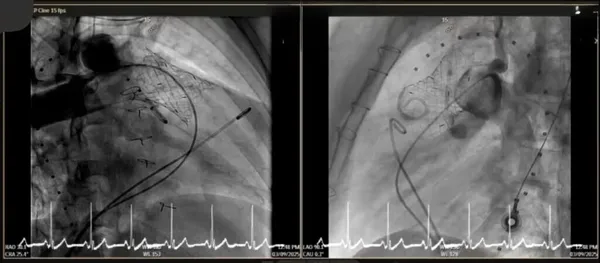

การใส่ลิ้นหัวใจพัลโมนิกเทียมผ่านสายสวนหัวใจ (Transcatheter pulmonary valve implantation; TPRI ) ในครั้งนี้ ทำผ่านทางหลอดเลือดดำใหญ่ บริเวณขาหนีบ จึงไม่ต้องผ่าตัดเปิดทรวงอก โดยกระบวนการรักษาและพักฟื้นผ่านไปได้ด้วยดี ไม่พบภาวะแทรกซ้อน ผู้ป่วยสามารถออกจากโรงพยาบาล 2 วันภายหลังการรักษา นับเป็นหนึ่งในความก้าวหน้าของนวัตกรรมการแพทย์เพื่อใช้รักษา ลดความเสี่ยงของภาวะแทรกซ้อนต่างๆ รวมถึงยกระดับคุณภาพชีวิตของผู้ป่วยได้

การผ่าตัดเปิดทรวงอกในแต่ละครั้ง จะก่อให้เกิดพังผืด (fibrous adhesion) เพิ่มความยากลำบาก และความเสี่ยงในการผ่าตัดมากขึ้น การรักษาผ่านทางสายสวนจึงเป็นทางเลือกที่จะลดความเสี่ยงนี้ลง อีกทั้งยังสามารถใส่ลิ้นพัลโมนิกเทียมชิ้นใหม่ทับแทนชิ้นเก่าได้ (valve in valve procedure)

การรักษาผ่านทางสายสวนครั้งนี้ได้รับความร่วมมือจากสหสาขาวิชาชีพ อาทิเช่น ศัลยแพทย์โรคหัวใจ ทรวงอก และหลอดเลือด กุมารแพทย์โรคหัวใจ อายุรแพทย์โรคหัวใจ วิสัญญีแพทย์ รังสีแพทย์ นักเทคโนโลยีหัวใจและทรวงอก รังสีแพทย์และนักรังสีการแพทย์ เจ้าหน้าที่และพยาบาลห้องสวนหัวใจ ห้องผ่าตัดศัลยกรรมทรวงอก หอผู้ป่วยวิกฤตศัลยกรรมหัวใจหลอดเลือด หอผู้ป่วยพิเศษ 5 พยาบาลหน่วยโรคหัวใจเด็กและผู้ใหญ่

การประสบความสำเร็จในการใส่ลิ้นหัวใจพัลโมนิกผ่านทางสายสวนหัวใจของคณะแพทยศาสตร์ มช. ในครั้งนี้ จึงนับเป็นความก้าวหน้าที่สำคัญในการนำเทคโนโลยีนวัตกรรมมาใช้ เพื่อยกระดับการดูแลรักษาผู้ป่วยให้มีคุณภาพสูงสุด มีความปลอดภัยมากขึ้น ลดความเจ็บปวดและระยะเวลาการพักฟื้น สามารถกลับคืนสู่ชีวิตปกติได้เร็ว เสริมสร้างคุณภาพชีวิตที่ดีในระยะยาว ซึ่งนับเป็นพันธกิจของคณะแพทยศาสตร์ มหาวิทยาลัยเชียงใหม่ ในการเป็นโรงเรียนแพทย์ในดวงใจ เพื่อความยั่งยืนด้านสุขภาวะ ด้วยนวัตกรรม